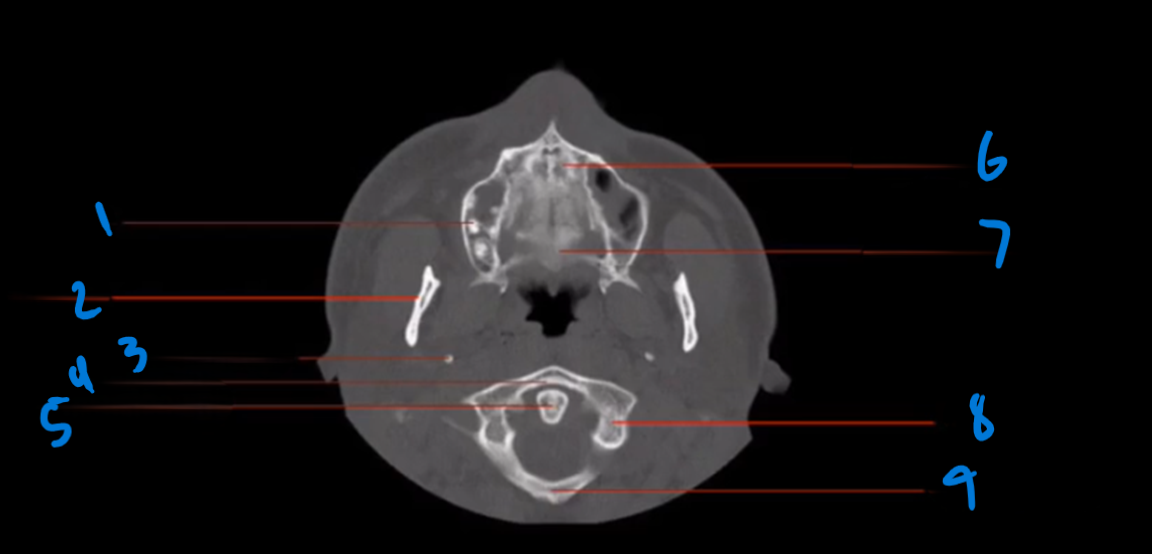

What is the landmark #1 called?

Nasal septum

What is landmark # 2 called?

Zygoma

What is landmark # 3 called?

Maxillary Sinus

WHat is landmark # 4 called?

Sphenoid Bone

What is landmark # 5 called?

Carotid Canal

Nasal bone

What is landmark # 6 called?

Maxillary Bone

WHat is landmark # 7 called?

Sphenoid Sinus

What is landmark # 8 called?

Mastoid air cells, Temporal bone